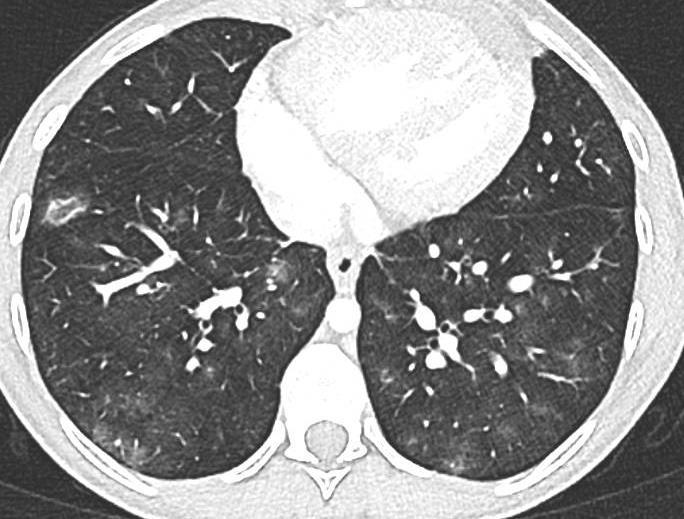

Acute Pediatric COVID-19: CT

21 Imaging of Covid 19 infection in children

3 Phases

Progressive: Diffuse GGO

Developed: Consolidation

Surr vasc congestion

Inflammation - adj alveoli

Alveoli fill with fluid/cells

• Patchy bilateral GGO, Consolidations or both

• Peripheral and lower lung zone predominance

• Bilateral & multifocal GGO, +/Consolidations or both

• Halo sign

• Peripheral and subpleural

• Bronchovascular thickening